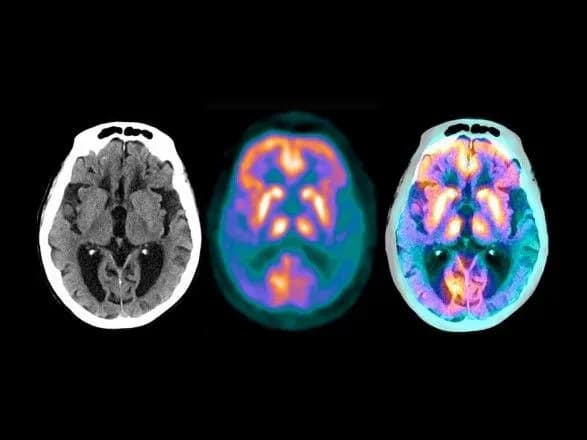

Повідомлення про неврологічних ускладнення у пацієнтів з COVID-19 і тих, у кого симптоми зберігаються після зникнення інфекції, стають все більш поширеними, що свідчить про те, що SARS-CoV-2 (вірус, що викликає COVID-19) може чинити тривалий вплив на функціонування мозку. Однак ще не зовсім зрозуміло, як вірус призводить до неврологічних проблем, наголошується в звіті.

У своєму дослідженні вчені за допомогою штучного інтелекту вивчили дані пацієнтів з хворобою Альцгеймера і COVID-19. Вони виміряли близькість між генами/білками пацієнтів з SARS-CoV-2 і генами, пов'язаними з декількома неврологічними захворюваннями, де більша близькість передбачає наявність пов'язаних або спільних шляхів захворювання. Дослідники також проаналізували генетичні фактори, які дозволили SARS-COV-2 інфікувати тканини і клітини мозку.

"Хоча дослідники виявили мало доказів того, що вірус націлений безпосередньо на мозок, вони виявили тісні мережеві зв'язки між вірусом і генами/білками, пов'язаними з декількома неврологічними захворюваннями, передусім з хворобою Альцгеймера, вказуючи на шляхи, за якими COVID-19 може призвести до деменції, подібної до хвороби Альцгеймера", - йдеться в повідомленні.

Далі вчені досліджували потенційний зв'язок між COVID-19 і нейрозапаленням і пошкодженням мікросудин головного мозку, які є відмінними ознаками хвороби Альцгеймера.

"Ми виявили, що інфекція SARS-CoV-2 значно змінила маркери хвороби Альцгеймера, залучені в запалення мозку", - вказав провідний автор дослідження доктор Фейсюн Чен.

"Ці дані показують, що вірус може впливати на кілька генів або шляхів, що беруть участь в нейрозапаленні і пошкодженні мікросудин головного мозку, що може призвести до когнітивних порушень, подібних до хвороби Альцгеймера", - додав він.

Патологоанатоми з медичного комплексу в Нью-Йорку The Mount Sinai Hospital, в епіцентрі глобальної пандемії COVID-19 торік, підготували один з найбільших і всебічних аналізів розтинів жертв COVID-19, відкривши безліч нових подробиць про хворобу. Так, при дослідженні мозку в певній кількості випадків були виявлені мікротромби з невеликими і неоднозначними ознаками загибелі тканин, викликаної закупоркою кровоносних судин як в периферичних, так і в глибоких частинах мозку. Ці дрібні мікроінфаркти можуть пояснити деякі психологічні зміни, що спостерігаються у деяких пацієнтів з позитивною реакцією на COVID-19, вказували тоді дослідники.